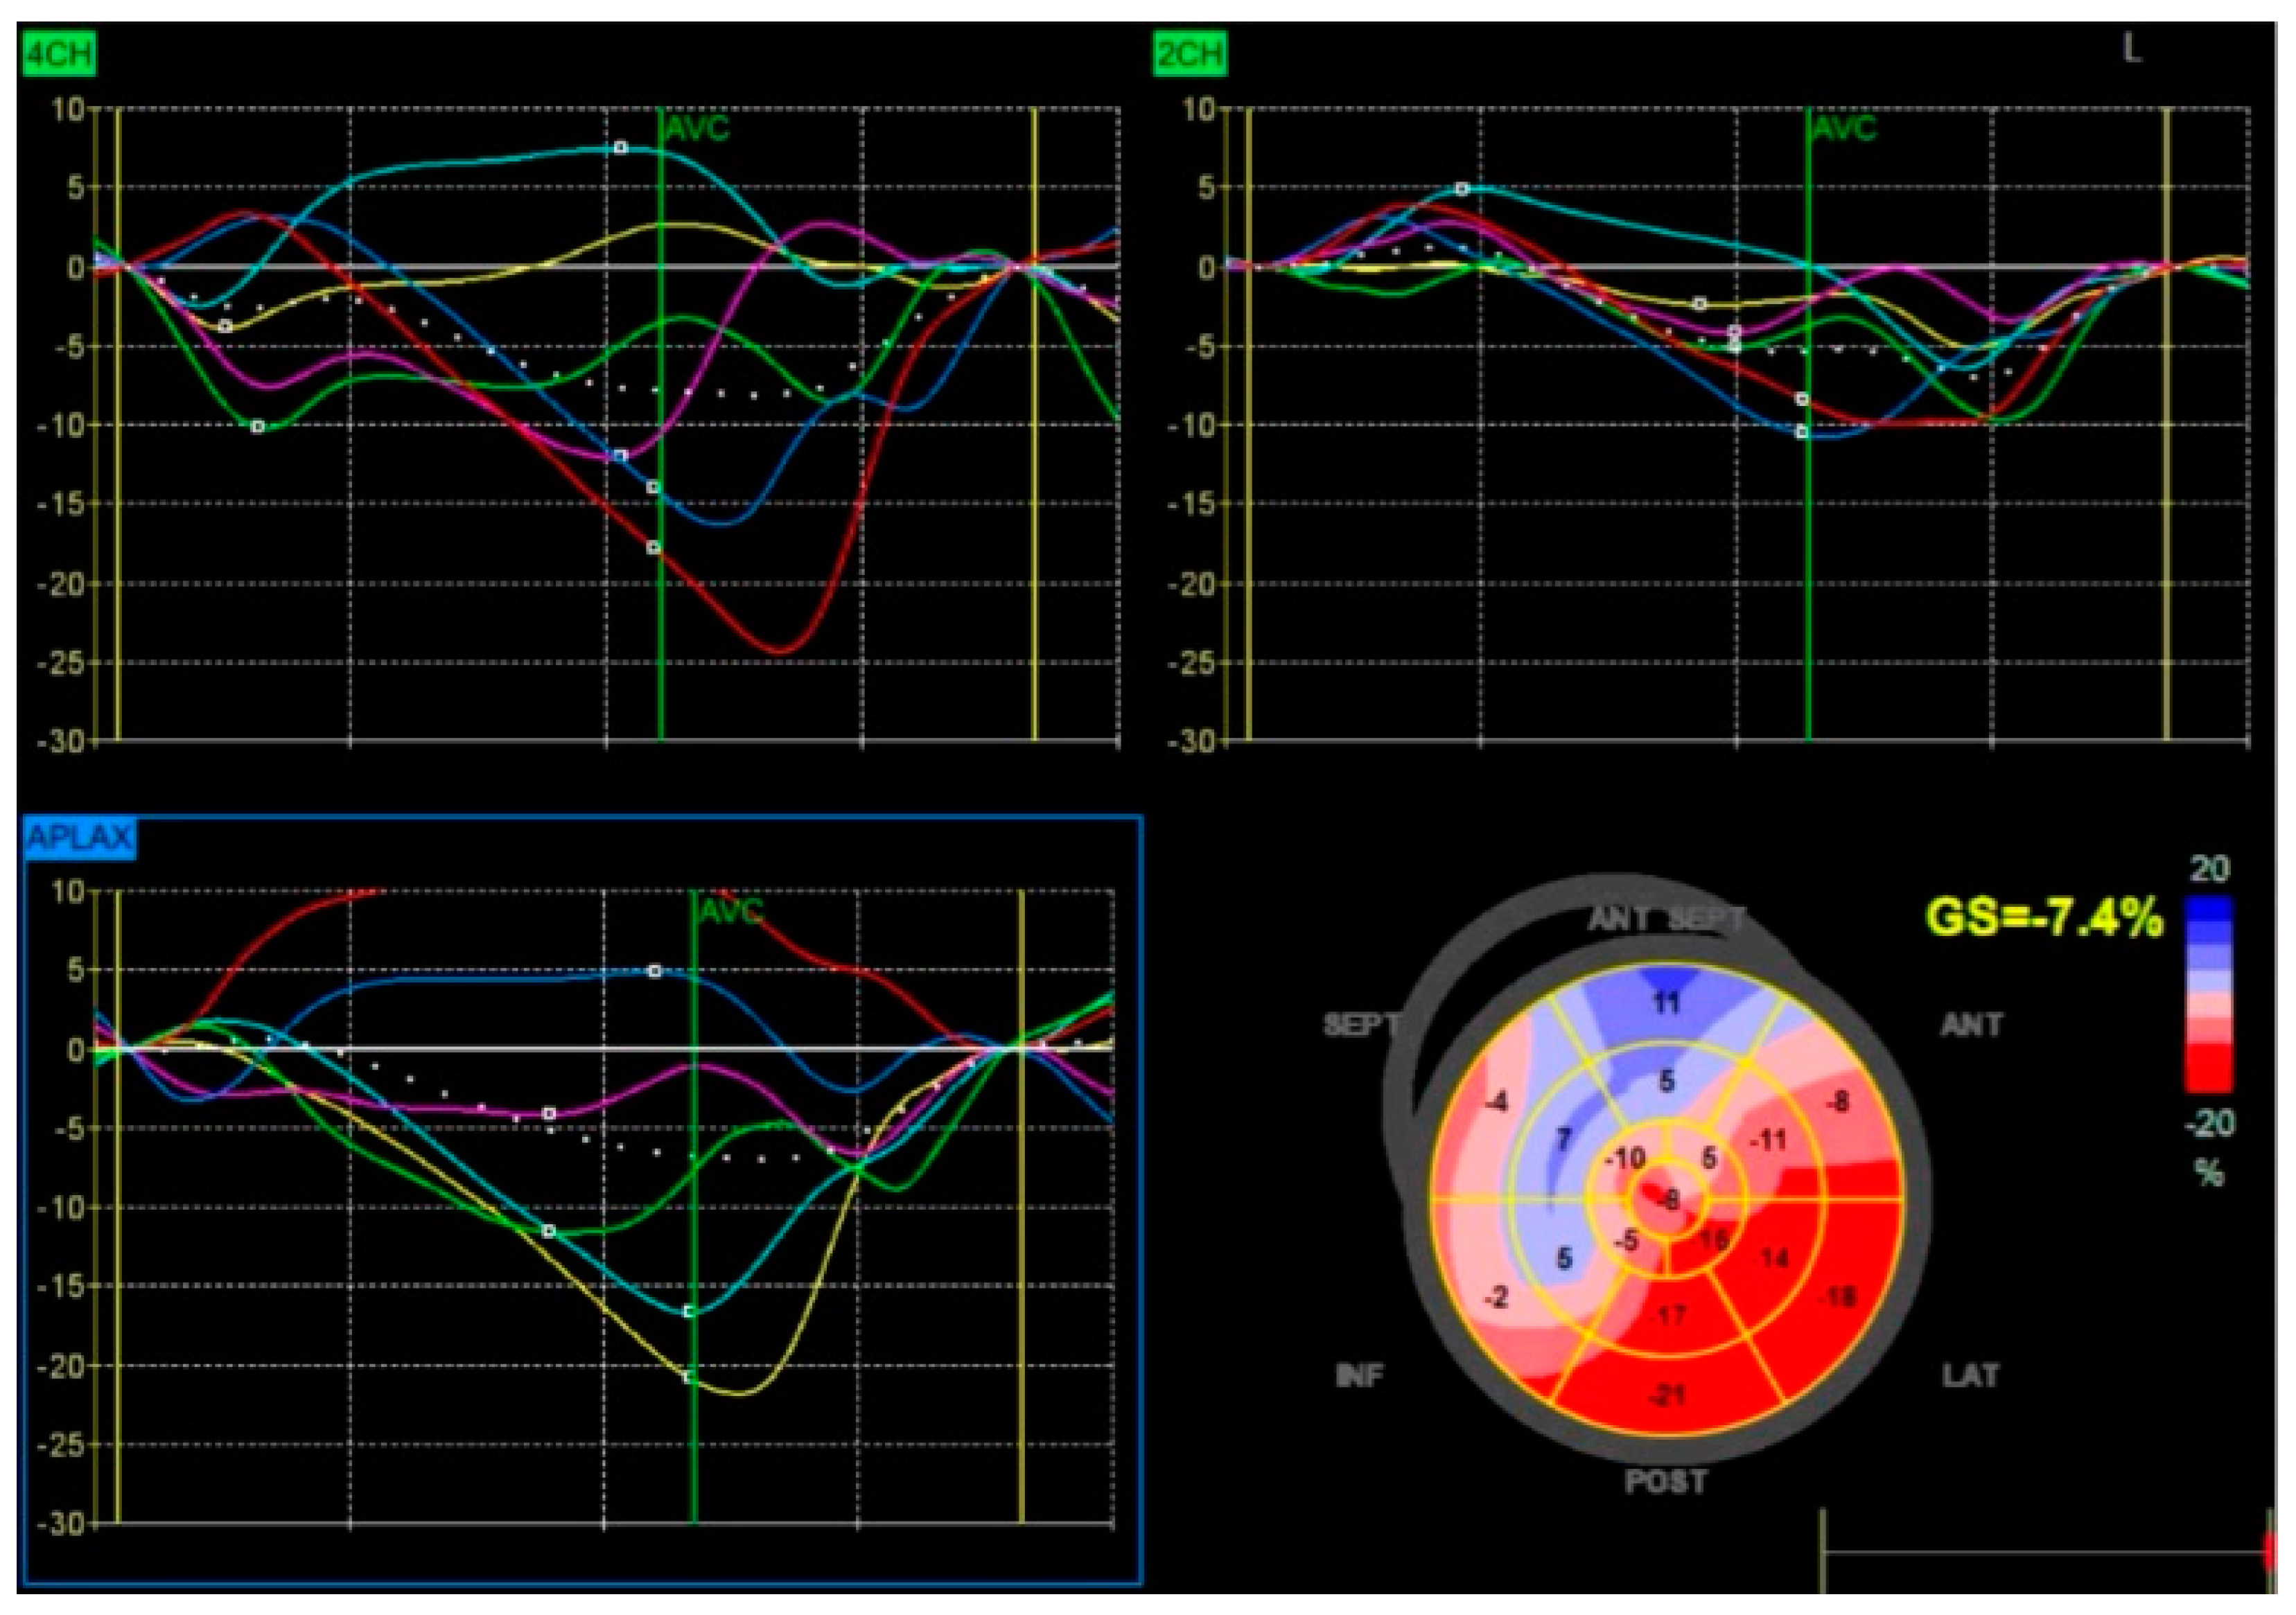

Advancements in imaging techniques such as Tissue Doppler Imaging (TDI), speckle-tracking echocardiography (STE), and global longitudinal strain (GLS) have improved the ability to quantify dyssynchrony, enabling better patient selection for resynchronization therapies.

3. Imaging Modalities for Assessing Dyssynchrony

Although a QRS duration of ≥130 milliseconds on electrocardiography is a key criterion for BBP suitability [16], echocardiographic advancements have greatly enhanced the assessment of ventricular mechanics and their response to treatment in patients with LBBB and HFrEF. Imaging plays a pivotal role in guiding patient selection for BBP or CRT, predicting treatment response, and monitoring the long-term success of resynchronization therapy [17]. The ability to detect subtle changes in myocardial mechanics, such as GLS improvements or reductions in septal-to-lateral delay, allows for individualized therapy optimization, ultimately improving patient outcomes [18] (Figure 5).

Speckle-Tracking Echocardiography: STE provides a refined evaluation of myocardial deformation by analyzing strain and strain rate. Unlike TDI, which measures myocardial velocities, STE evaluates the percentage change in myocardial length during contraction, offering a more precise assessment of ventricular mechanics [20].

In LBBB, GLS is often significantly reduced due to asynchronous myocardial contraction. STE generates strain maps illustrating areas of delayed or paradoxical motion. The interventricular septum typically exhibits reduced or negative strain in early systole, while the lateral wall demonstrates delayed peak strain, underscoring the extent of dyssynchrony [21]. This quantitative analysis aids in determining a patient’s likelihood of responding to resynchronization therapy.

STE has several advantages over TDI, including angle independence and greater accuracy in detecting subclinical LV dysfunction. Improvements in GLS following BBP or CRT are strongly correlated with better clinical outcomes, including enhanced LVEF, reduced ventricular volumes, and improved functional capacity [22].

In addition to volumetric changes, myocardial strain analysis provides valuable insights into BBP’s role in reversing dyssynchrony. STE has shown that BBP significantly improves GLS by enhancing the coordination of myocardial contraction. This improvement is closely linked to the restoration of electrical synchrony, aligning the contraction of the septum and lateral wall. Notably, GLS has been identified as a strong predictor of clinical outcomes in heart failure, with improvements following BBP correlating with better functional capacity, fewer symptoms, and increased survival [49].

Figure 5. Speckle-tracking echocardiography showing global longitudinal strain analysis. The strain curves indicate significant dyssynchrony, and the bullseye plot reveals severely impaired GLS, suggesting advanced myocardial dysfunction.